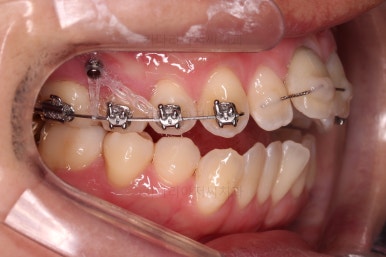

난이도가 매우 높은 치료인만큼 미니스크류의 구성과 장치 구성도 매우 복잡했는데요.

윗니 어금니를 뒤로 밀면서 앵글씨 2급 부정교합을 개선해 주고, 높낮이를 조절하면서 개방교합을 개선해 줍니다.

이제는 발치를 했기 때문에 한시가 급합니다.

기간이 길어지면 길어질수록 퇴축하므로 적절한 위치가 잡히면 바로 임플란트를 할 수 있도록 대비를 합니다.

보철 전문의 원장님과 상의하여 가장 적합한 치아 사이즈 및 위치를 정해나가고요.

개방교합도 많이 다물어졌고, 2급 부정교합도 매우 많이 개선되었네요.

임플란트 가능 시점이 점점 다가오는데요.

임플란트를 한 번 하게되면 많은 치아 움직임은 없어야 되기 때문에, 앞니의 높이, 입매, 교합 등등 모든 점에서 평가가 진행됩니다.